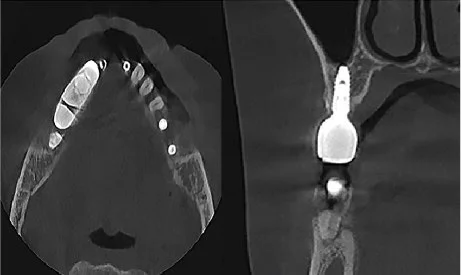

Precizie în diagnostic: voxel de 200 µm pentru CBCT și rezoluție panoramică de 120 µm/pixel.

Versatilitate clinică: potrivit pentru implantologie, chirurgie orală, sinus lift, planificare pre-protetică.

Software intuitiv: vizualizare MPR/3D și compatibilitate CAD/CAM (3Shape, Exoplan, NobelGuide).